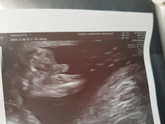

3 августа 2023 03:55 Прошли 2 скрининг, слава Богу, всё нормально. Только видимо растормошили маську, а может я разволновалась так, что тахикардию выдали. 2 недели назад не было. Позже ещё схожу на УЗИ по месту, проверим по тахикардии. Подтвердили пол ( фото).

3 августа 2023 16:43 Утром на скрининге, малыш частил СБ 172. Думала, ну может моё волнение сказалось, или растормошили. УЗИ-стка ещё меня спросила, волнуюсь ли я. Поставила тахикардию в заключении, хотя по доплеру, вчера и до этого дома мерила, было всё ок, даже иногда … Читать далее